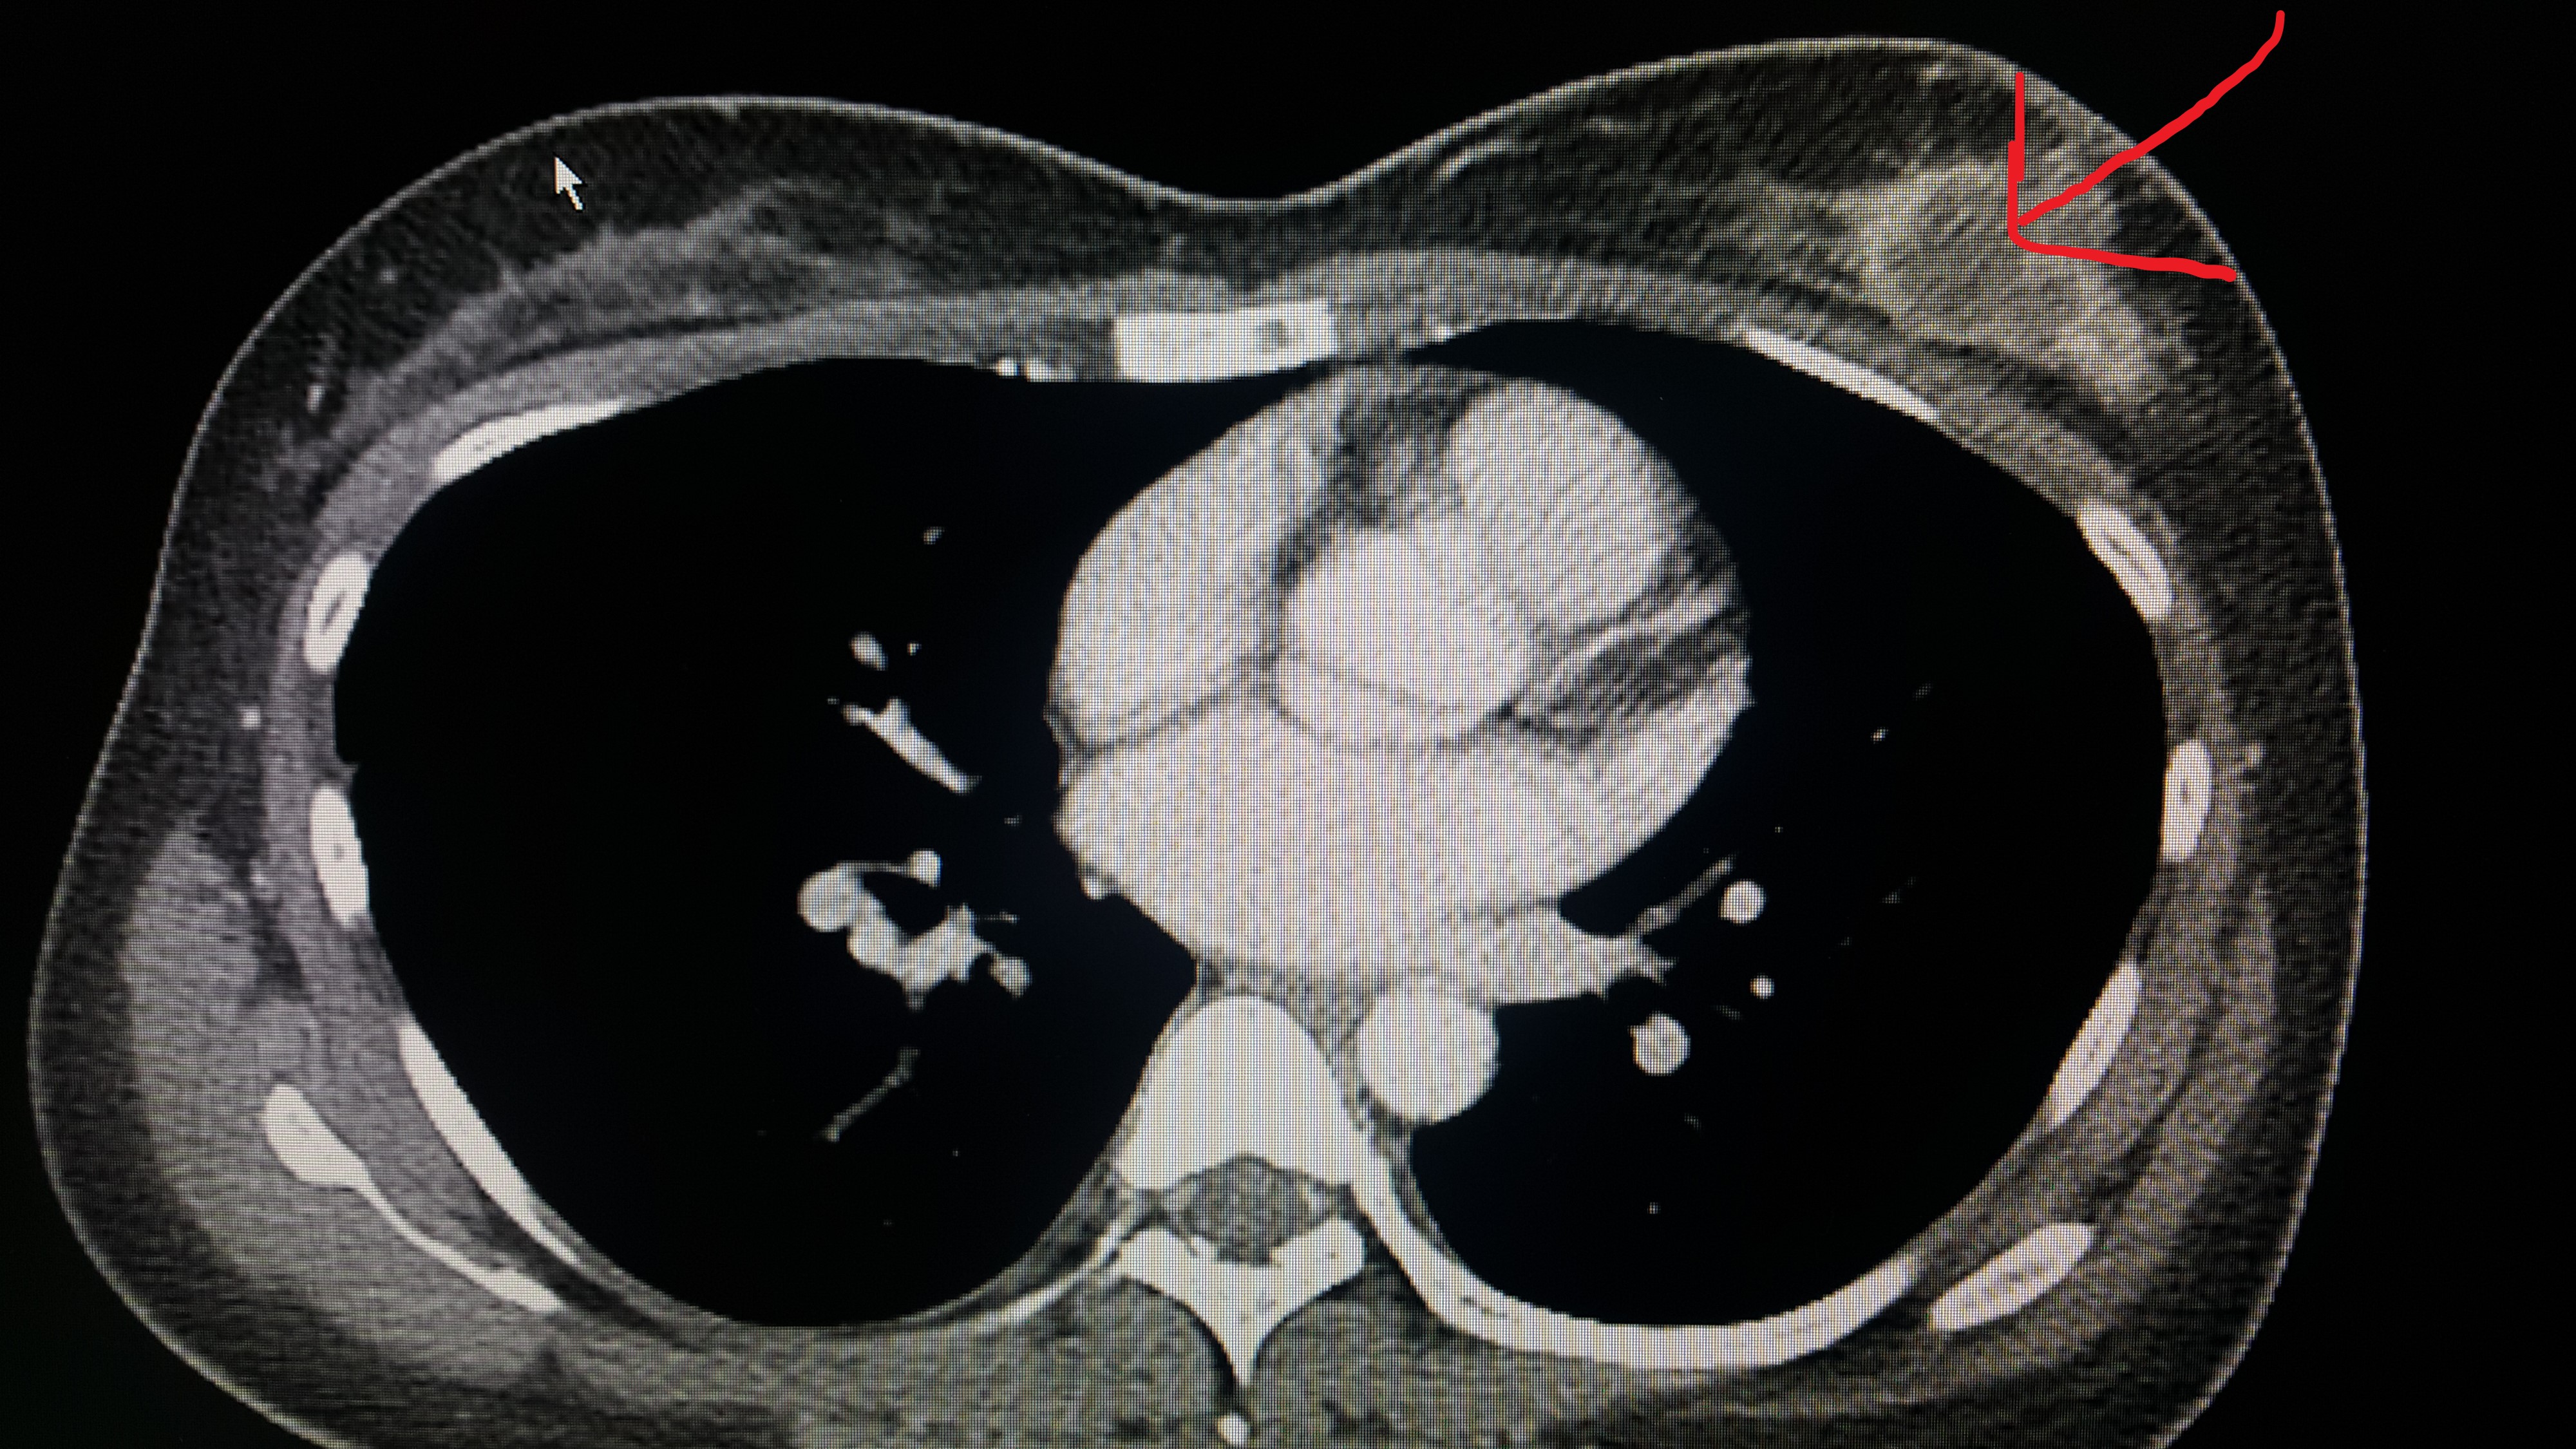

원발성 병소인 유방암이다. 환자의 좌측 유방에서 병변을 확인할 수 있다. 유방에서 생긴 암이 증식에 증식을 거듭하여 다른 장기인 간에까지 옮겨간 것이다.